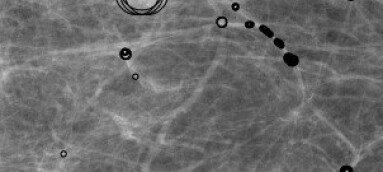

Comparison to the a contrario method of Grosjean and Moisan [4]. This a contrario method is designed to detect spots in colored noise textures, and was applied to the detection of tumors in mammographies. This detection algorithm is the only other one computing NFAs, and we can directly compare them to ours. The detection results on a real mammography (having a tumor) are shown in Figure 3. With our method the tumor is detected with a much significant NFA (NFA of whereas in [4] NFA of ). Our self-similar anomaly detection method shows fewer false detections, actually corresponding to rare events like the crossings of arterials.